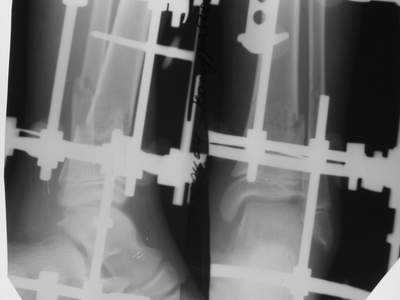

A> Это сросшийся перелом малоберцовой кости. И ложный сустав

A> н\3 б\берцовой кости.

Нашел в комп-ре схожий случай:

1) з/репозиция, 2) фиксация 2 спицами, 3) аппарат, 4) фиксационные

спицы удалены...

А можно было наложить аппарат и по поводу ложного сустава...

По крайней мере не было бы укорочения (пусть и в 2 см)...